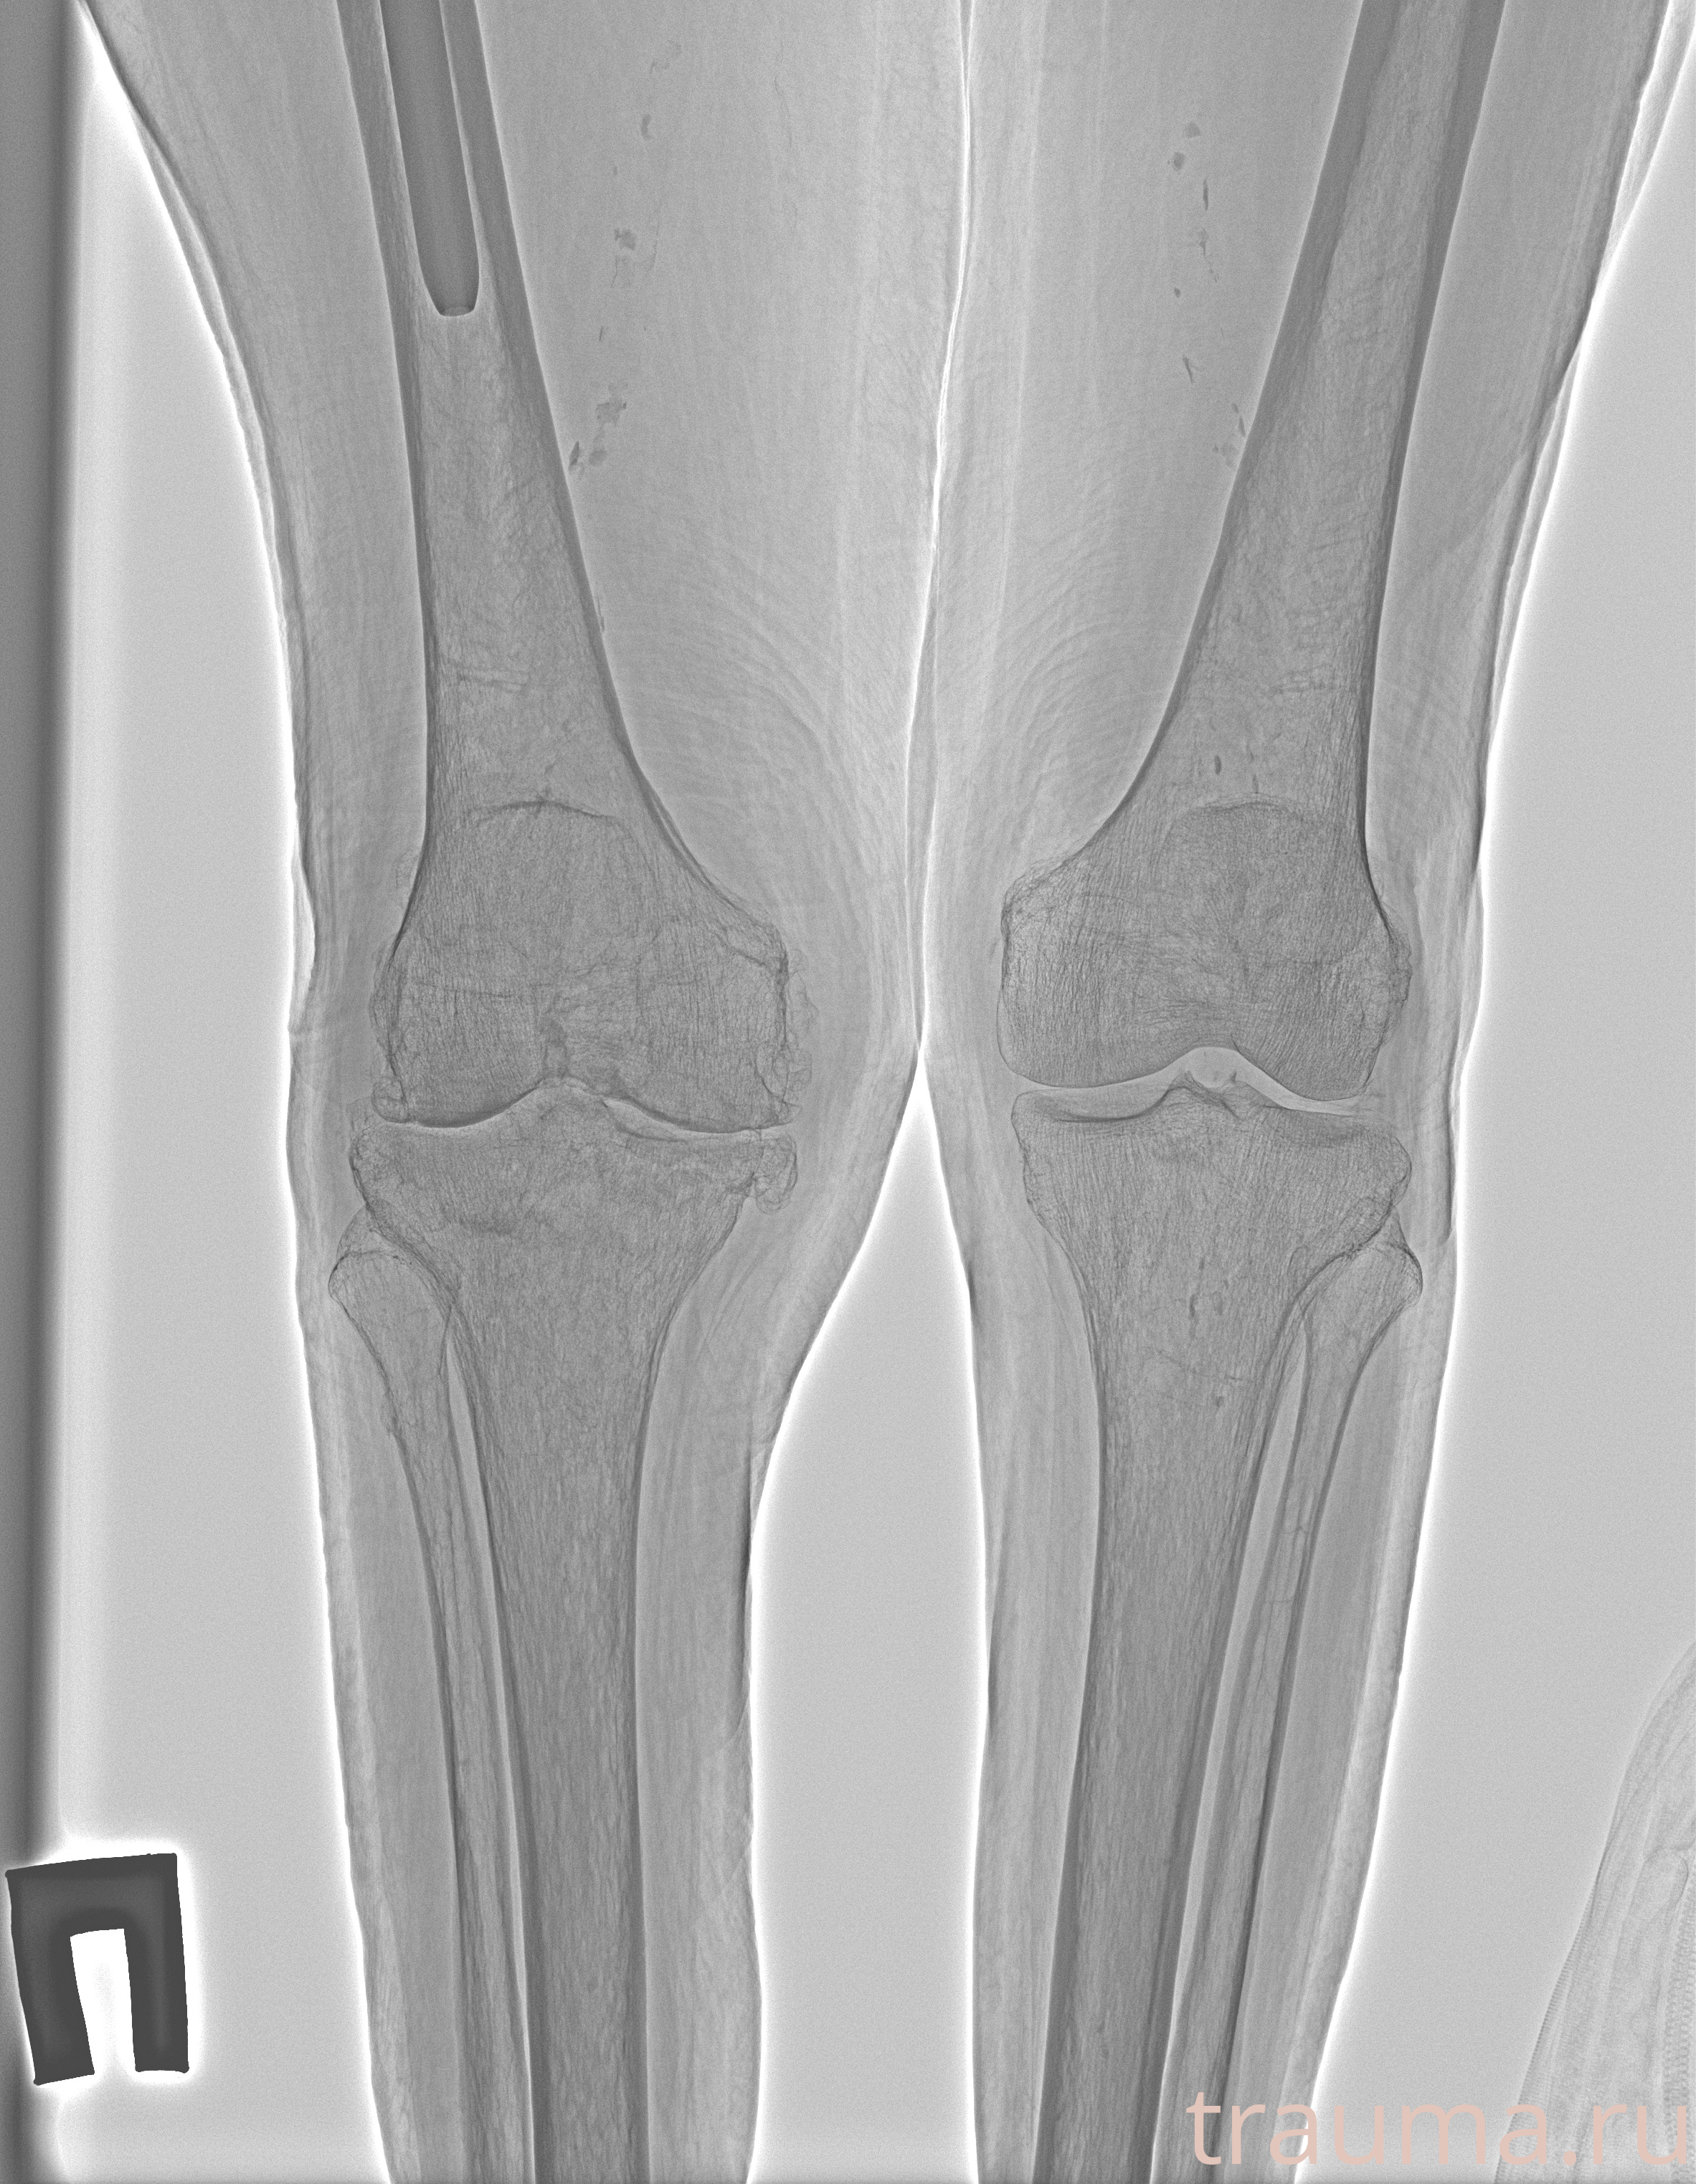

Рентгенограммы

Рентген на дому: по вашему адресу приезжает врач-рентгенолог, травматолог-ортопед с мобильным рентгеновским аппаратом, проводит диагностику травмы или заболевания, делает необходимые рентгенограммы, дает рекомендации по дальнейшему лечению. Получить качественные снимки в домашних условиях возможно благодаря уникальной методике, разработанной МосРентген Центром для института  Склифосовского